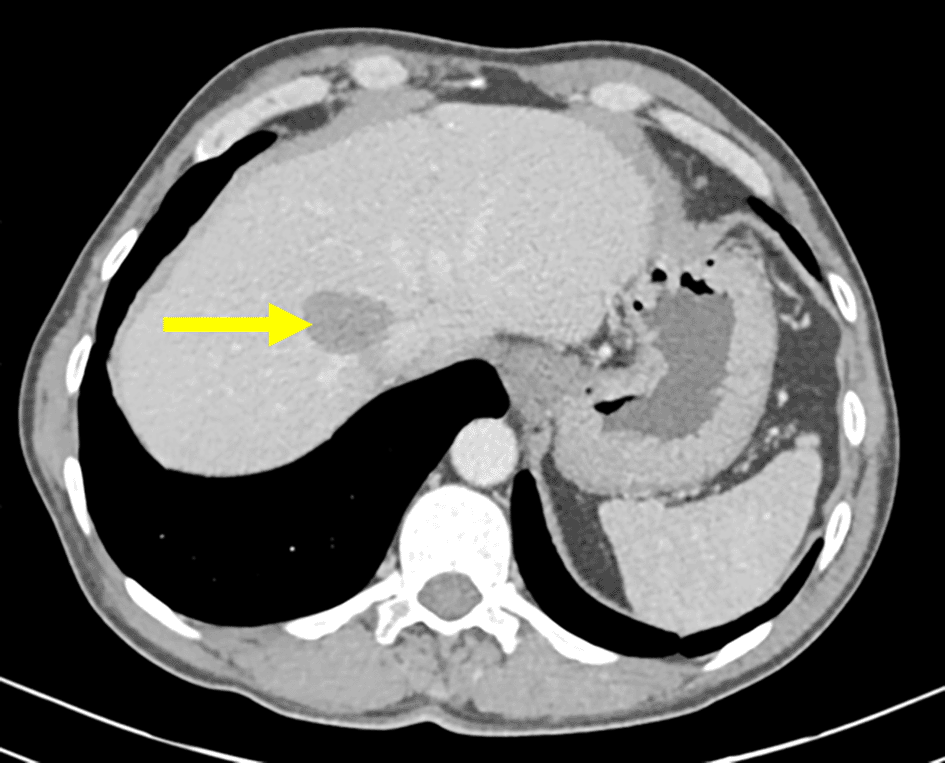

The patient was followed up in the abdominal surgery department for a multiple organ hydatidosis that included 13 hydatid cysts: the lungs, the liver (Figure 1), the left heart ventricle, the left kidney (Figure 2), the abdomen cavity, muscles (psoas, adductors), and subcutaneous gluteal area. The majority of these cysts was already treated surgically and some are still pending to be removed (Table 1). The patient has received oral Albendazole 400 mg twice-daily for 2 years.

Renal involvement is also rare (2–3%) and it is usually associated to a disseminated disease, they are most commonly asymptomatic, like the case of our patient. The diagnosis was made by an abdominal CT which has a sensitivity of 98% to diagnose hydatid disease.6